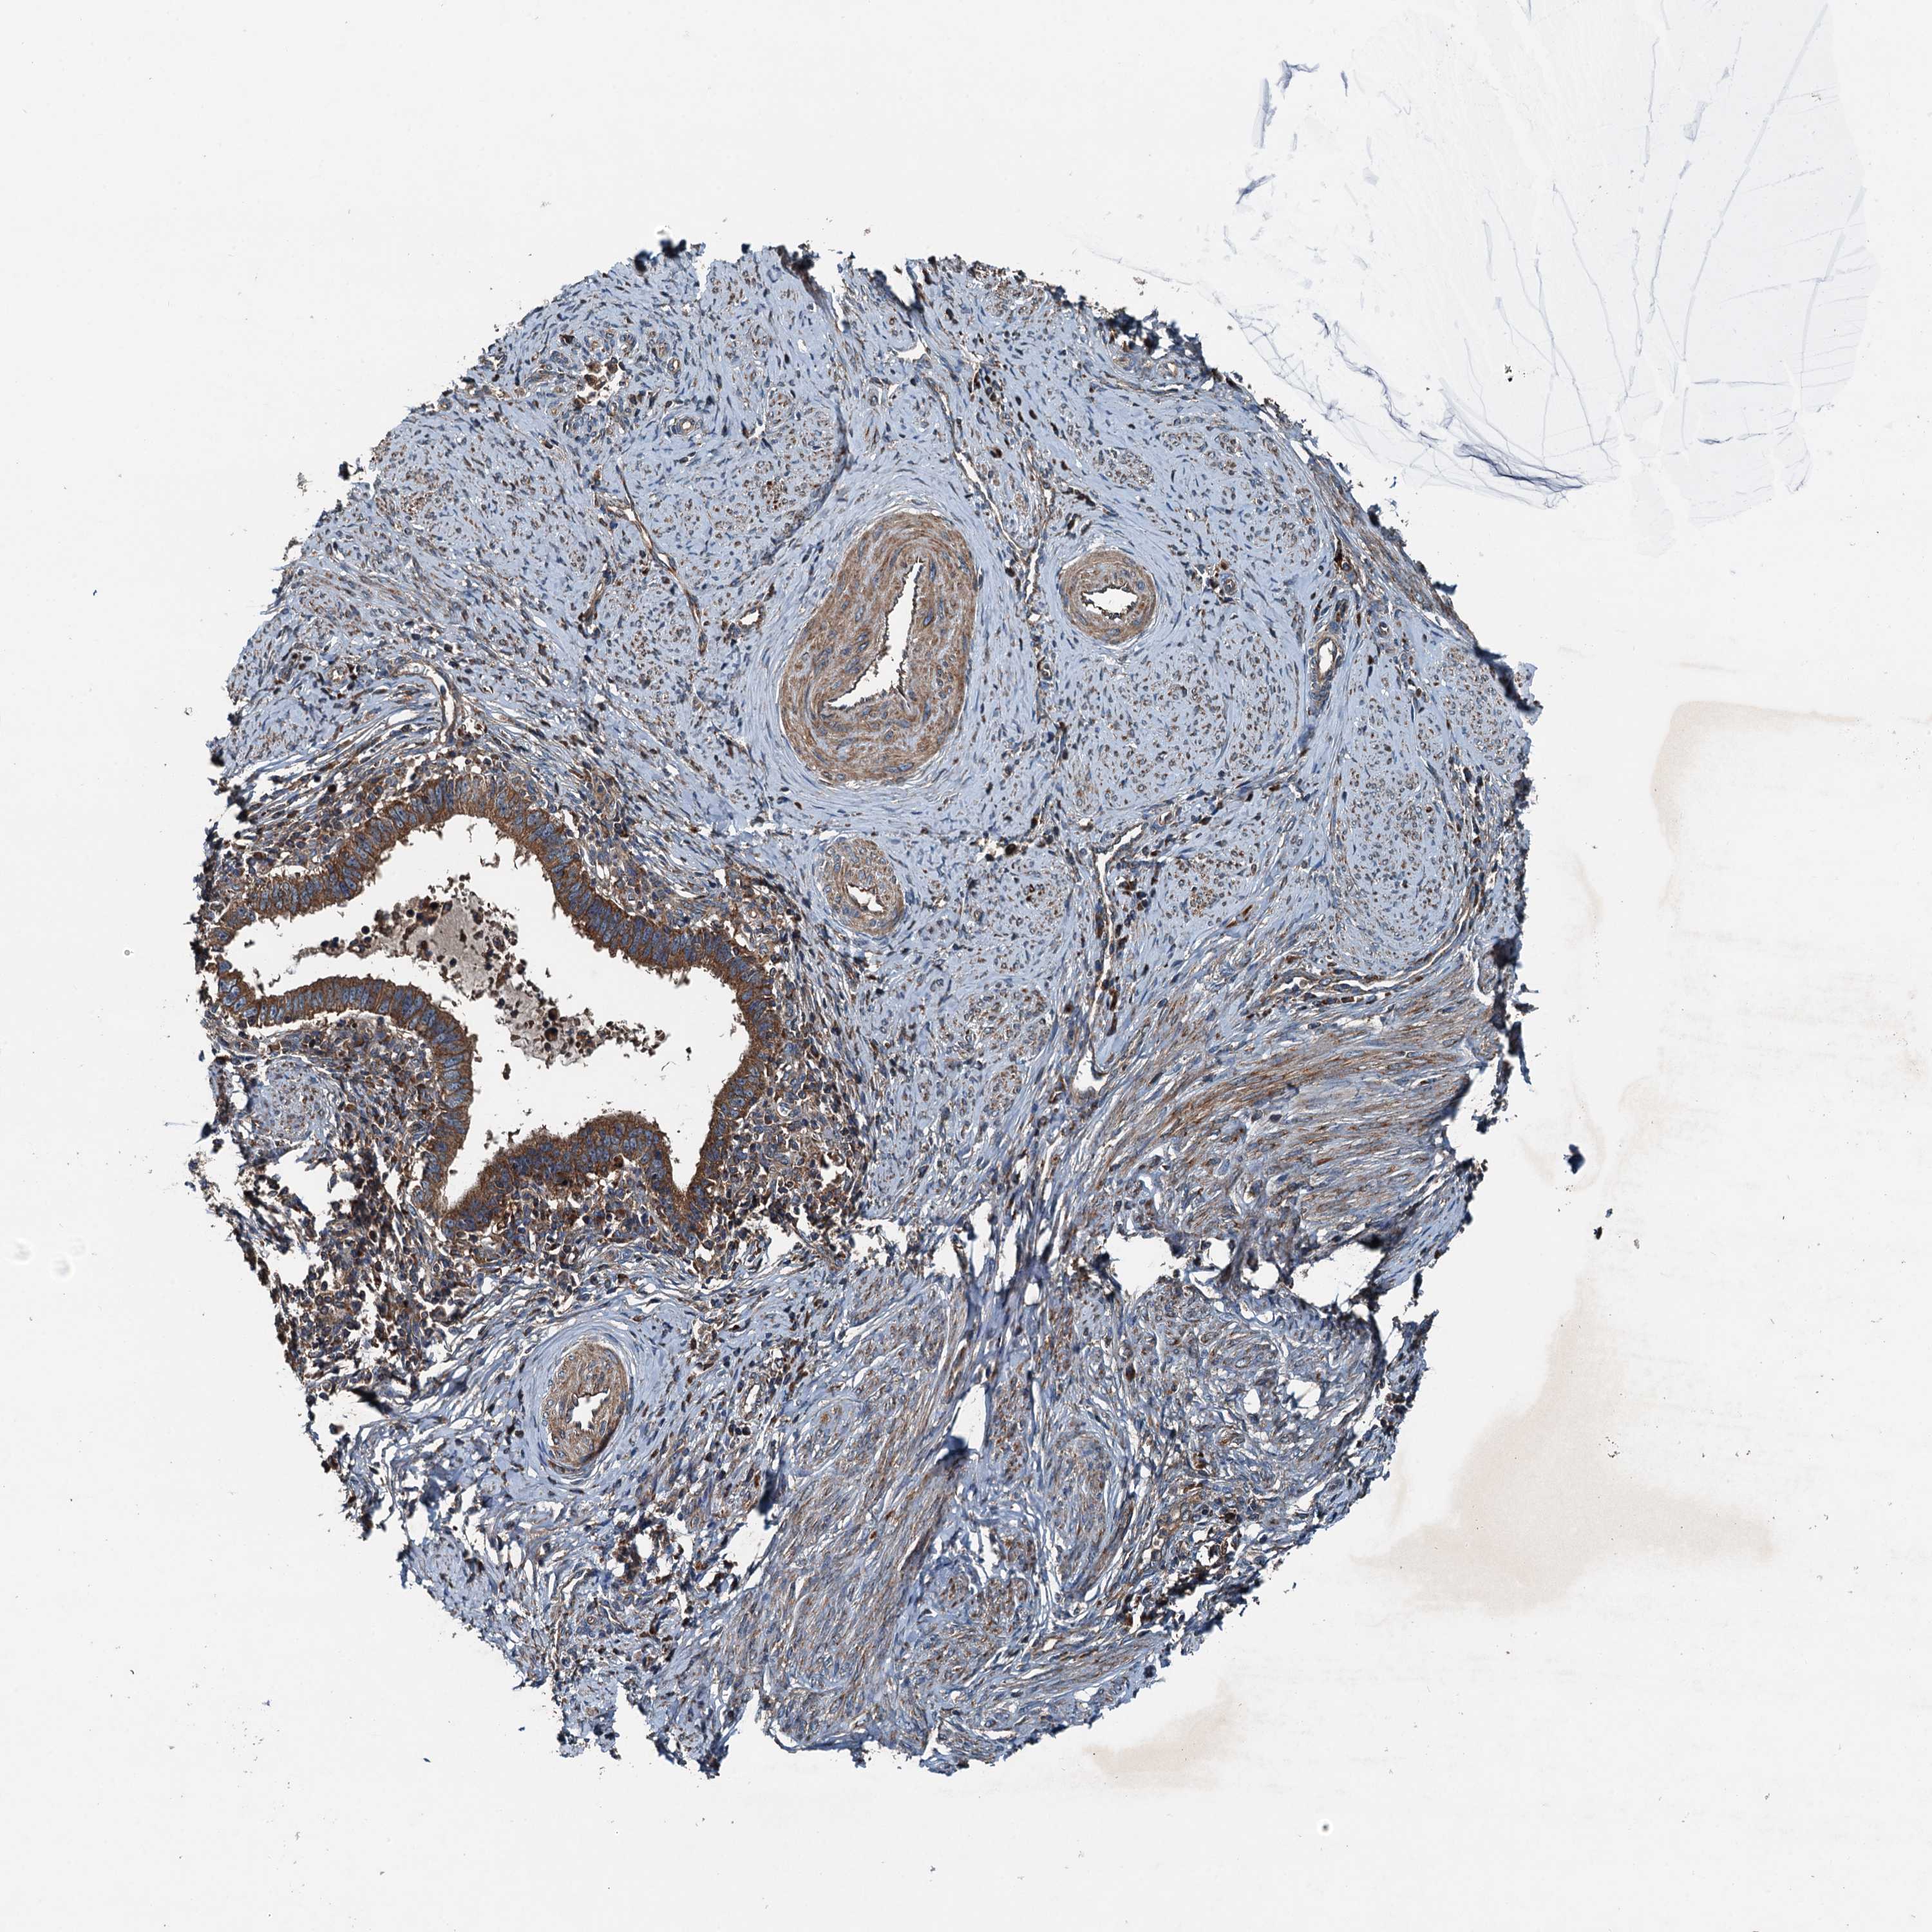

CERVICAL CANCER - Protein expressioni

A mouse-over function shows sample information and annotation data. Click on an image to view it in a full screen mode. Samples can be filtered based on level of antibody staining by selecting one or several of the following categories: high, medium, low and not detected. The assay and annotation is described here.

Note that samples used for immunohistochemistry by the Human Protein Atlas do not correspond to samples in the TCGA dataset.

Antibody stainingi

Antibody staining in the annotated cell types in the current human tissue is reported as not detected, low, medium, or high, based on conventional immunohistochemistry profiling in selected tissues. This score is based on the combination of the staining intensity and fraction of stained cells.

Each image is clickable and will lead to virtual microscopy that enables deeper exploration of all samples and also displays staining intensity scores, fraction scores and subcellular localization as well as patient and tissue information for each sample.

Antibody HPA041227

Staining

High

Medium

Low

Not detected

Intensity

Strong

Moderate

Weak

Negative

Quantity

>75%

75%-25%

<25%

None

Location

Nuclear

Cytoplasmic/membranous

Cytoplasmic/membranous,nuclear

Squamous cell carcinoma, NOS

Adenocarcinoma, NOS